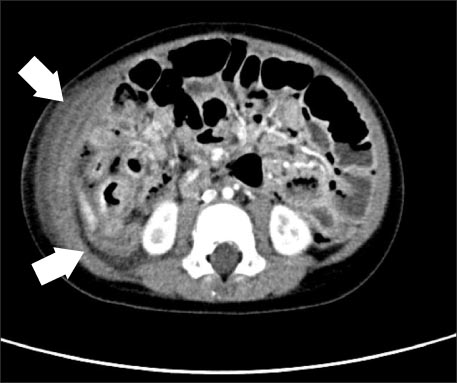

Fig. 5

White arrowhead indicates intestinal tissue; Black arrowhead indicates gastric tissue; Black arrow indicates serosa tissue and inflammation (H&E, ×40).

Fig. 5 White arrowhead indicates intestinal tissue; Black arrowhead indicates gastric tissue; Black arrow indicates serosa tissue and inflammation (H&E, ×40).